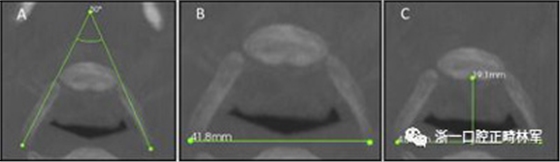

下頜骨前后角度的測量(下頜AP角),下頜橫角(TA下頜骨)和舌骨橫角(TA舌骨)。測量結(jié)果列于表I和圖1-4中。

圖3.A,舌骨橫角; B,LL舌骨; C,AP舌骨。

圖4. A,下頜橫角; B,LL下頜骨; C,AP下頜骨。